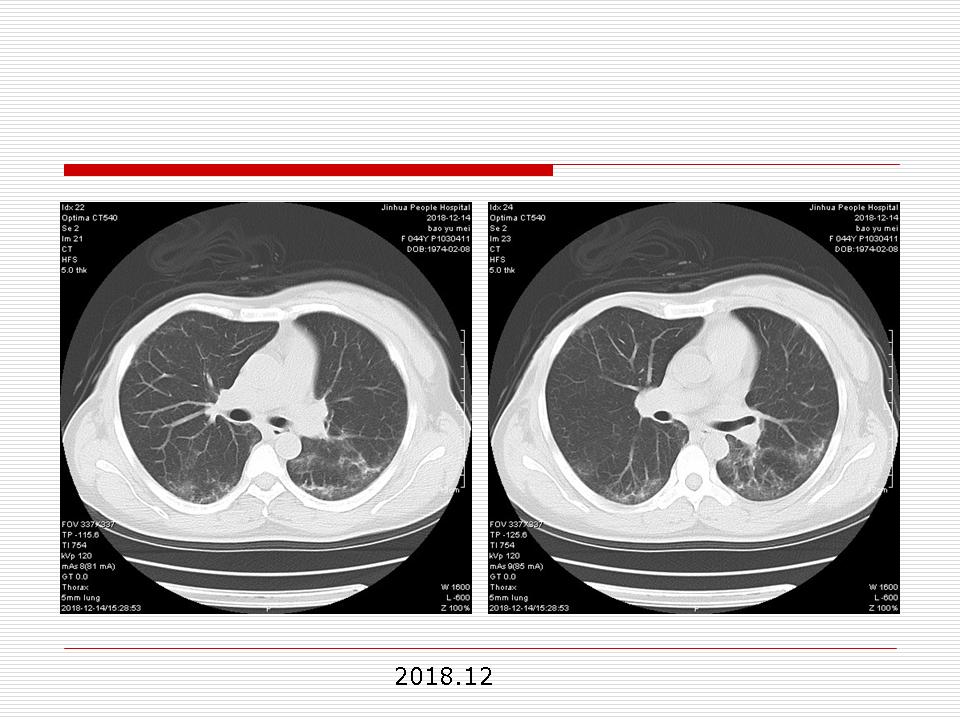

肺部阴影永恒且最重需要鉴别的是:到底是炎症还是肿瘤?但临床的病例中的影像表现难以界定或有些肿瘤特征,同时又有些炎症特点是非常常见的情况。作为临床医生我们怎么去总结分析,并找到之所以是炎症或之所以是肿瘤的细微差别或特点非常重要,也非常有用。2019.12.7浙江省2019年胸心外科学学术年会在宁波召开时,我的临床病例分析与经验总结<那些像肺癌的炎症与像炎症的肺癌>获得在大会交流的机会,以下为该PPT的内容,与你分享,希望对同道有益,有借鉴与启迪。若有探讨与进一不完善的建议,欢迎文末留言讨论: